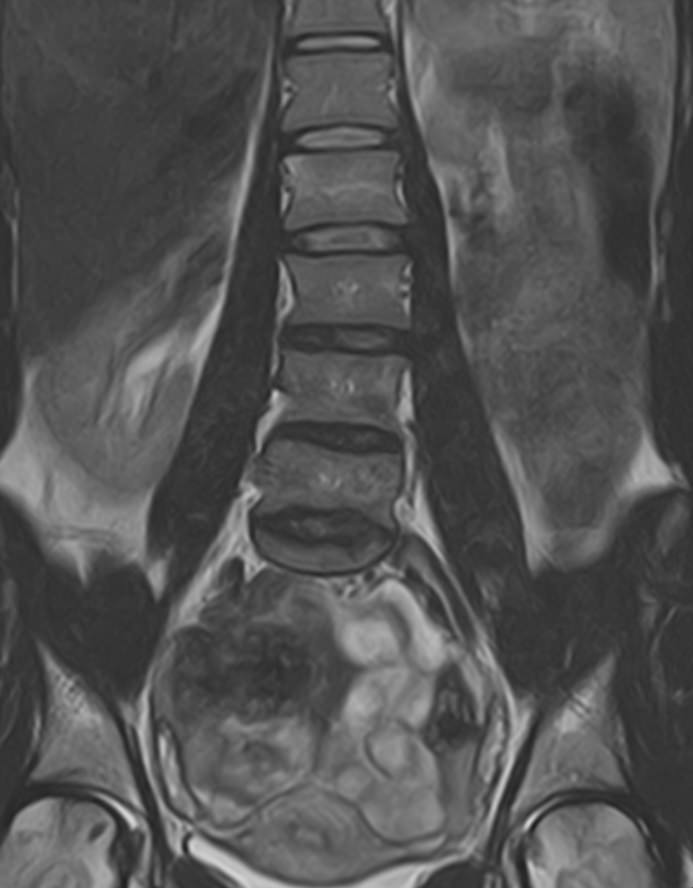

Магнитно-резонансная томография является современным, высокоинформативным и доступным методом обследования позвоночника. МРТ позволяет оценить состояние костных структур позвонков, спинного мозга, нервных корешков и окружающих мягких тканей.

В клинике «Доступная медицина» выполняется МРТ различных отделов позвоночника. В зависимости от уровня поражения можно провести МР томографию шейного отдела, грудного отдела, пояснично-крестцового отдела позвоночника и копчика.